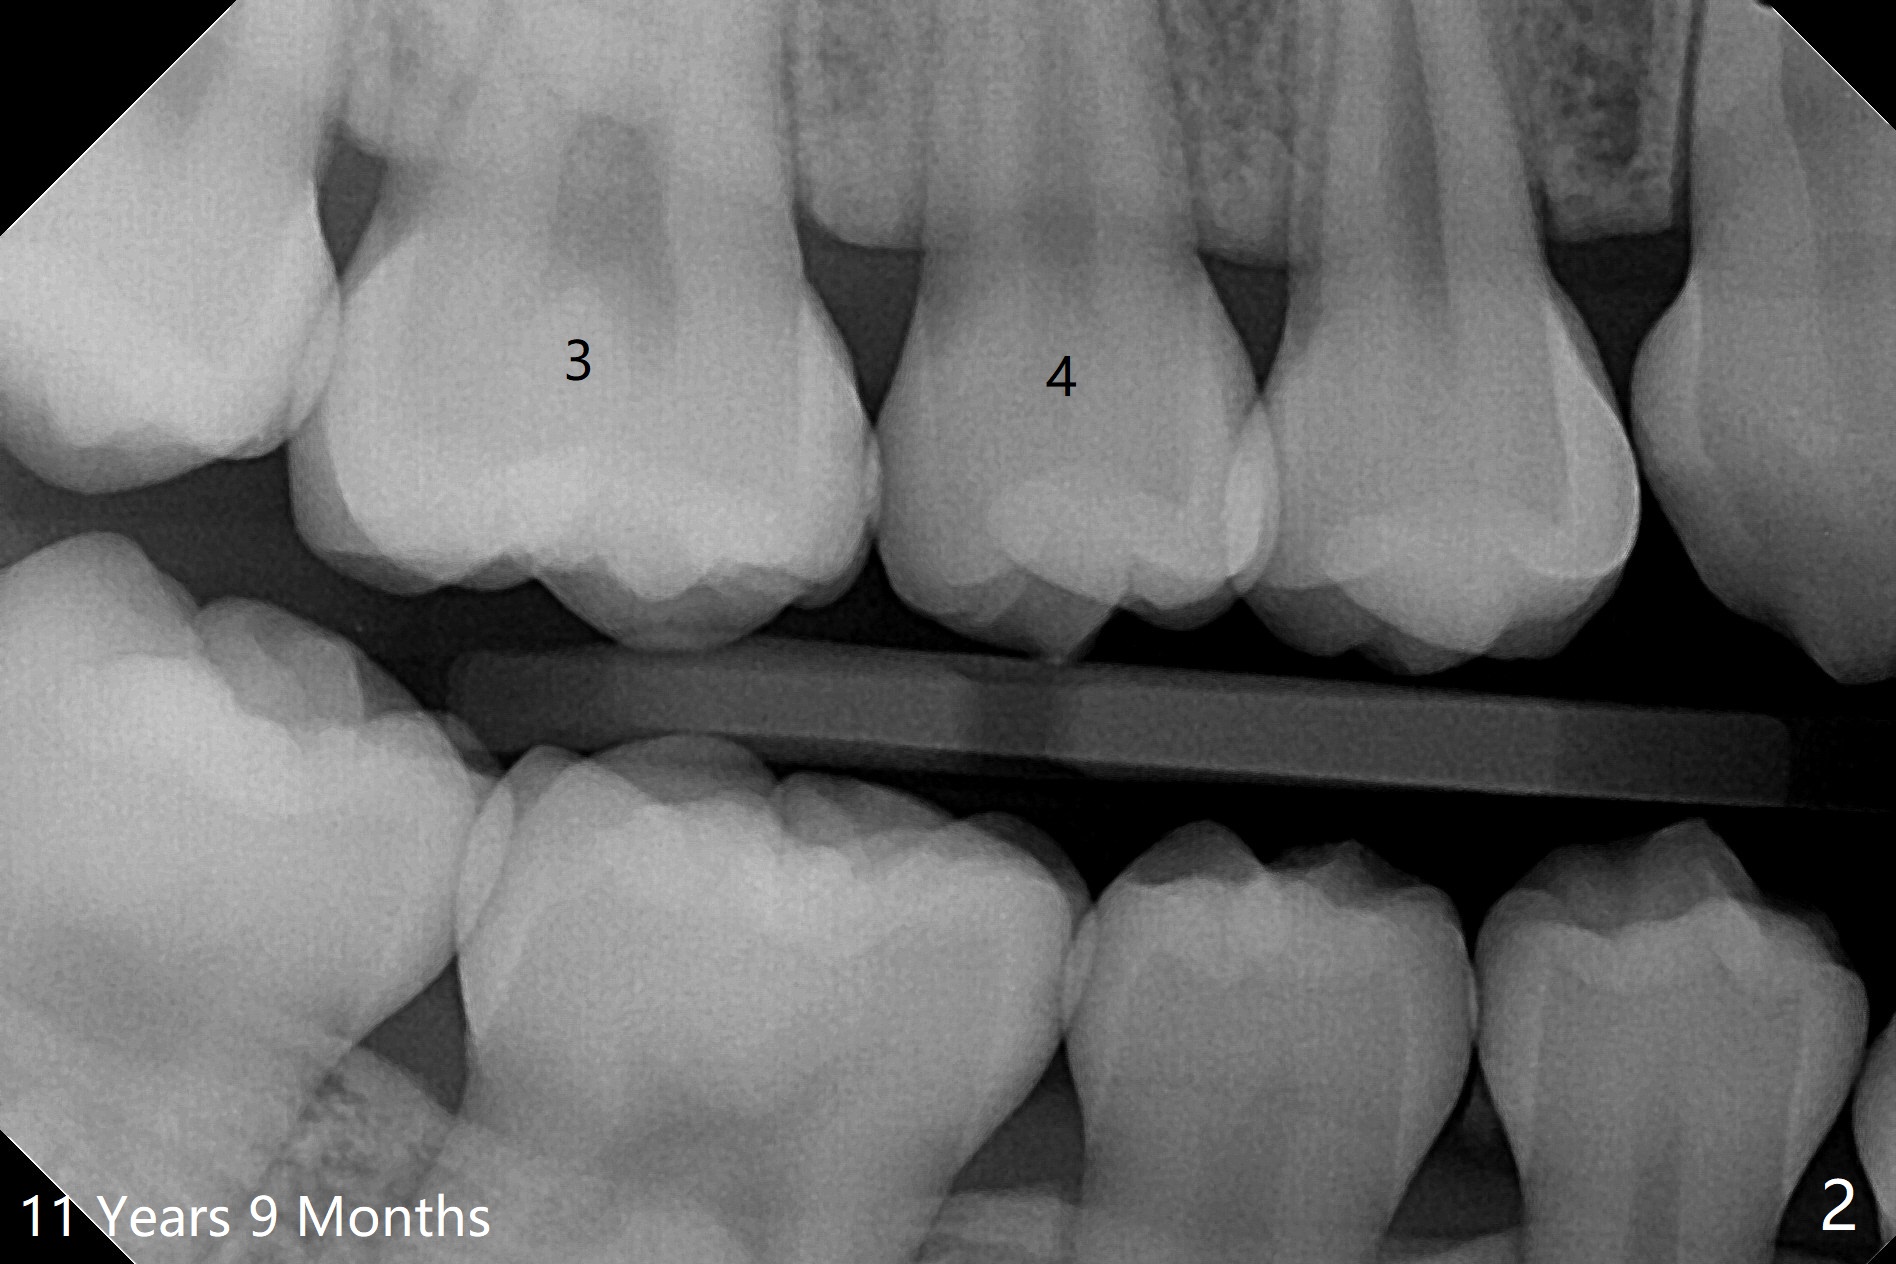

10岁半女孩上颌第二乳磨牙远中龋好像造成第一恒磨牙近中龋(图一)。要求妈妈当乳磨牙脱落时,带她回来补牙。由于新冠病毒,女孩1年3个月后才回来,右上第二前磨牙已经基本完成萌出,右上6近中龋被掩盖了(图二),而左侧前磨牙腭侧部分萌出(图三,四),磨牙近中龋(表现为脱钙,图四:箭头)正好暴露。塞入gingival retraction cord(图五:C)和wedge (W),去龋,填入树脂,两牙之间通过牙线(F),光固化。之后不需要抛光。